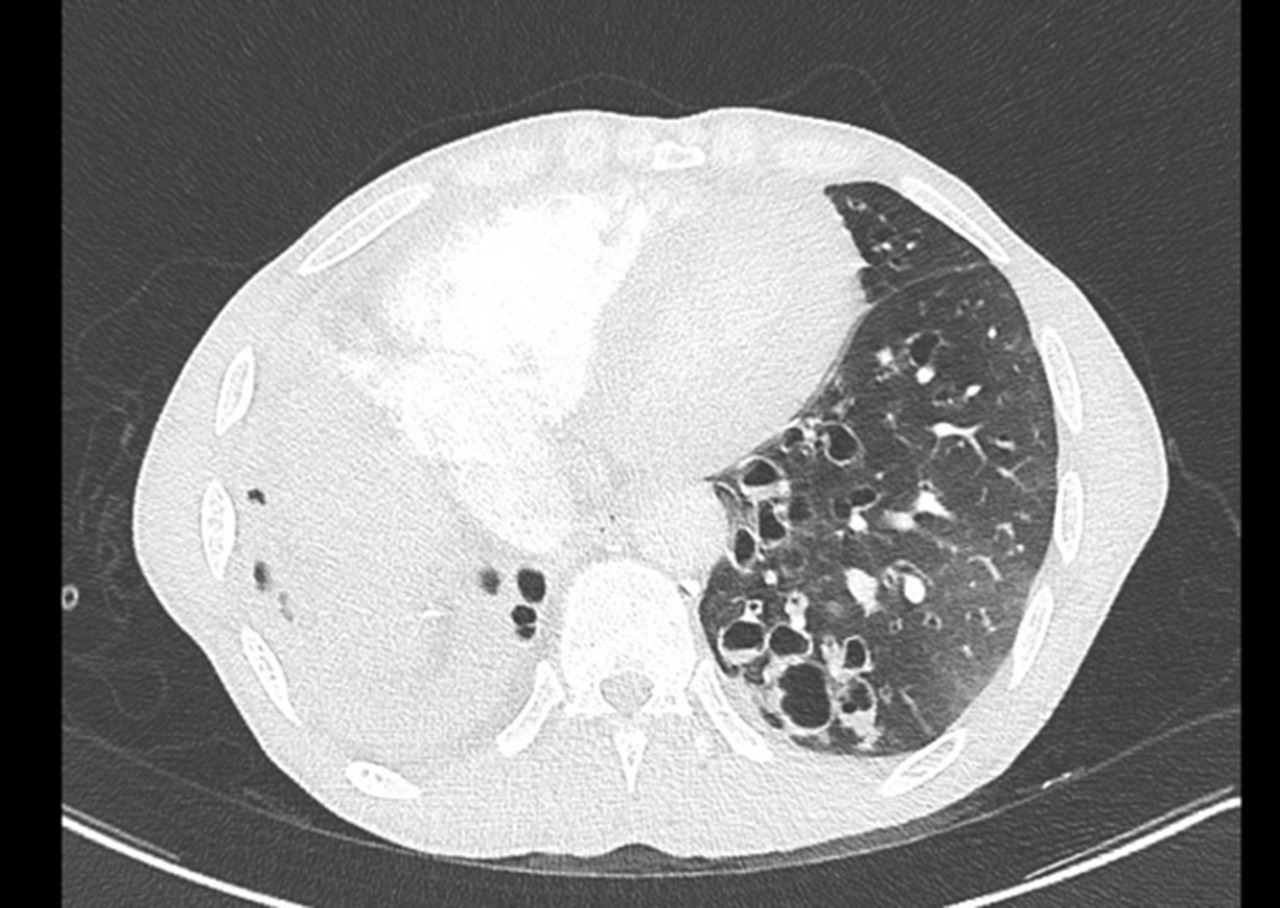

Vous êtes interne de garde aux urgences. Un patient de 71 ans est adressé par son médecin traitant pour dyspnée aiguë.

À l’arrivée, les constantes du patient sont : pression artérielle (PA) = 167/119 mmHg ; fréquence cardiaque (FC) = 114/min ; température (T) = 37,2 °C ; saturation en oxygène (SpO2) = 82 % en air ambiant ; fréquence respiratoire (FR) 30/min.

Présence fréquente d’épanchement pleural en cas d’insuffisance cardiaque mais généralement indolore.